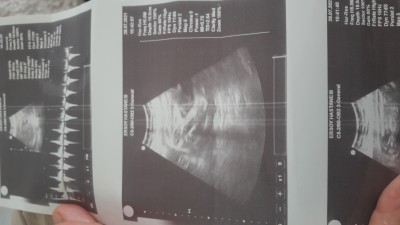

kizlar cinsiyet tahmini alabilir miyiz

30 haftalik ama hala belli değil bi erkek bi kiz diolar

Valla hicbir şey görünmüyor. Ama 30 haftaya kadar gorememisseniz ben kız diye tahmin ediyorum kızlar cinsiyeti daha geç gösteriyor. Tabi Allah bilir

Kız canm eminim

Kalp ritminden